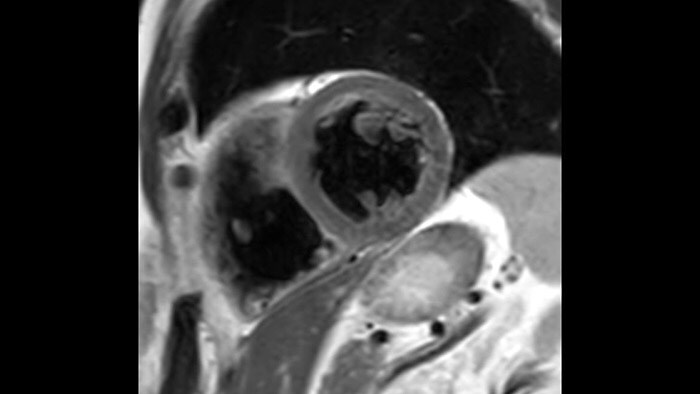

Mr Cardiac Imaging Philips Healthcare